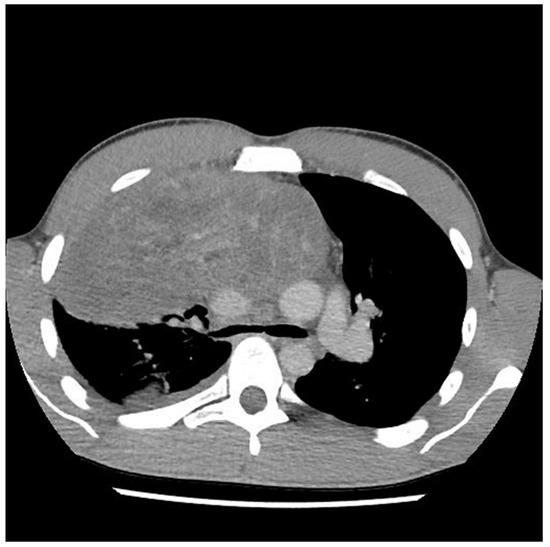

A sternotomy was performed using an oscillating saw. A plane was developed between the pericardial fat and pericardium at the level of the inferior vena cava and carried towards the left side of the tumor. Entering the left pleural space allowed release of the tumor from its left lateral attachments and identification of the left phrenic nerve. Fortunately, despite the preoperative CT (Figure 2 and Figure 3) suggesting encasement of the left subclavian artery, distracting the tumor to the right revealed it could be unwrapped and peeled off this vessel, allowing perseveration of it.

Figure 3.

Computed tomography (CT) scan image of mediastinal mass after two cycles of chemotherapy showing encasement of left subclavian artery.

The preoperative CT (Figure 1, Figure 2 and Figure 3) identified the involvement of three critical structures: (1) left subclavian artery, (2) right hilum of the lung and (3) SVC. Interestingly, only the encasement of the SVC was confirmed at the time of the surgery. The tumor enveloped the left subclavian on either side but could be peeled off, allowing preservation of the vessel. The tumor abutted the right hilum of the lung but maintained a potential space, so the lesion could simply be lifted off this region. The mass was densely adherent to the lung parenchyma, which was released with cautery. This resulted in a postoperative air leak, which was resolved with conservative management. The encasement of the SVC was the greatest operative challenge. Because the tumor significantly distorted the anatomy of the heart, the SVC was misidentified at the time of surgery, both by direct inspection and TEE evaluation. In retrospect, the use of adjunct techniques, such as a bubble study or the introduction of a wire under direct visualization, could have been helpful in ascertaining the structure intraoperatively. Transaction would have still been required for en bloc resection, but immediate reconstruction of the vessel would have then been possible.